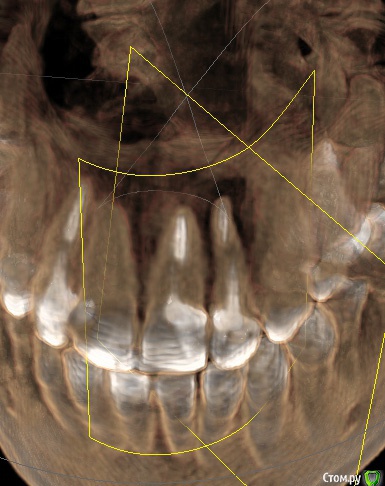

Ankazabolevshaya Опубликовано 28 мая, 2016 Поделиться Опубликовано 28 мая, 2016 Здравствуйте, уважаемые врачи! Очень сильно нуждаюсь в вашей помощи. В 2013 мне лечили два передних зуба (клык и передний). Пломбировали каналы, но коронки не ставили. Этой зимой я почувствовала боль в передних зубах в районе челюсти. Раздражение в дёснах. Резь. Потом вылез какой-то пупырь на десне. Я думала, что это стоматит. Не верила тем, кто мне говорил про нужность обзорного снимка. Признаю свою глупость. Теперь, после КТ оказалось что у меня сломаны эти каналы, а под левым клыком пустота. А пупырь, как мне сказали - это выход свища.Мне предложили зуб удалять. Как-то восстанавливать эту пустоту. Потом делать имплантацию. Есть ли сегодня технологии, позволяющие восстанавливать это пространство под зубом без его удаления, с последующей коронкой на него? И ещё один вопрос: могло ли все это случится из-за какой-нибудь заразы, занесенной во время лечения этих двух зубов в 2013г. ? Так же был момент ранения слизистой левой ноздри, как раз над свищем, который на десне. Просто очень часто слизистая иссыхала в одном месте и я травмировала слизистую. Буду очень благодарна за ответ. От меня в клинике ждут решения, а я переживаю, что улыбка испортится с искусственным зубом. Зуб этот свой очень люблю. Анна. Ссылка на комментарий

red_butler Опубликовано 28 мая, 2016 Поделиться Опубликовано 28 мая, 2016 Спасибо! Можете пояснить, Вы думаете, что зуб можно спасти? если судить только по снимкам, то да 1 Ссылка на комментарий

red_butler Опубликовано 29 мая, 2016 Поделиться Опубликовано 29 мая, 2016 а скажите, как по Вашему, это киста прикорневая? Или челюсть разрушена? Нужно восстановление челюсти? это не важно и корень ведь сломан, поставить под коронки всё равно можно? перелома не увидел И еще последнее, как Вы относитесь к процедуре - депофорез? В моём случае стоит в эту торону смотреть? бесполезно 2 Ссылка на комментарий

red_butler Опубликовано 29 мая, 2016 Поделиться Опубликовано 29 мая, 2016 Как же доказать им что нет на самом деле этого перелома (или корневого канала)? Мы видим только часть срезов Кт, а доктора на очном осмотре и ситуацию в полости рта.Сходите еще на пару консультаций. Как по-вашему – скорее всего виноват тот врач (как раз это тот врач, который настаивает на удалении и на переломе канала), который пломбировал каналы этого зуба в 2013? Или я? Сколько по времени такая штука на корне в среднем формируется? Было и ранение слизистой носа было так же ранение десны во время читки нитью, глубокое и долго заживало. Теперь уже не разобраться, виноват ли врач? Вы не правильно понимаете цели форума, Мы отвечаем на вопросы "что делать" Да и раз депофорез бесполезен, то что с Вашей точки зрения предпочтительнее сегодня в моём случае? Лазер или иссечение корня? Повторное лечение корневого канала. 3 Ссылка на комментарий